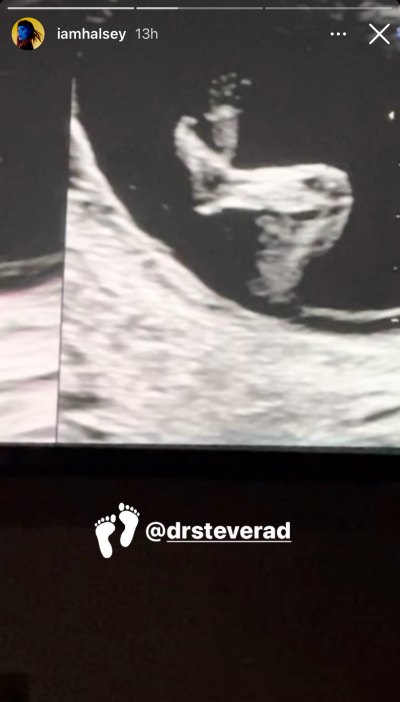

Chillin’ like a villain! Pregnant Halsey shared the cutest ultrasound image of baby No. 1‘s feet while relaxing with their legs crossed via her Instagram Stories on Friday, January 29.

The 26-year-old added a footprint emoji on the adorable photo and tagged Dr. Steve Rad, an obstetrician specializing in maternal and fetal medicine who works with A-list patients. According to the physician’s latest Instagram post, he and his team aided Jessica Biel when she gave birth to her and husband Justin Timberlake‘s second child, son Phineas, in 2020. The Los Angeles-based doc also treated Chrissy Teigen amid her last pregnancy with husband John Legend, which tragically ended in a miscarriage in September 2020.